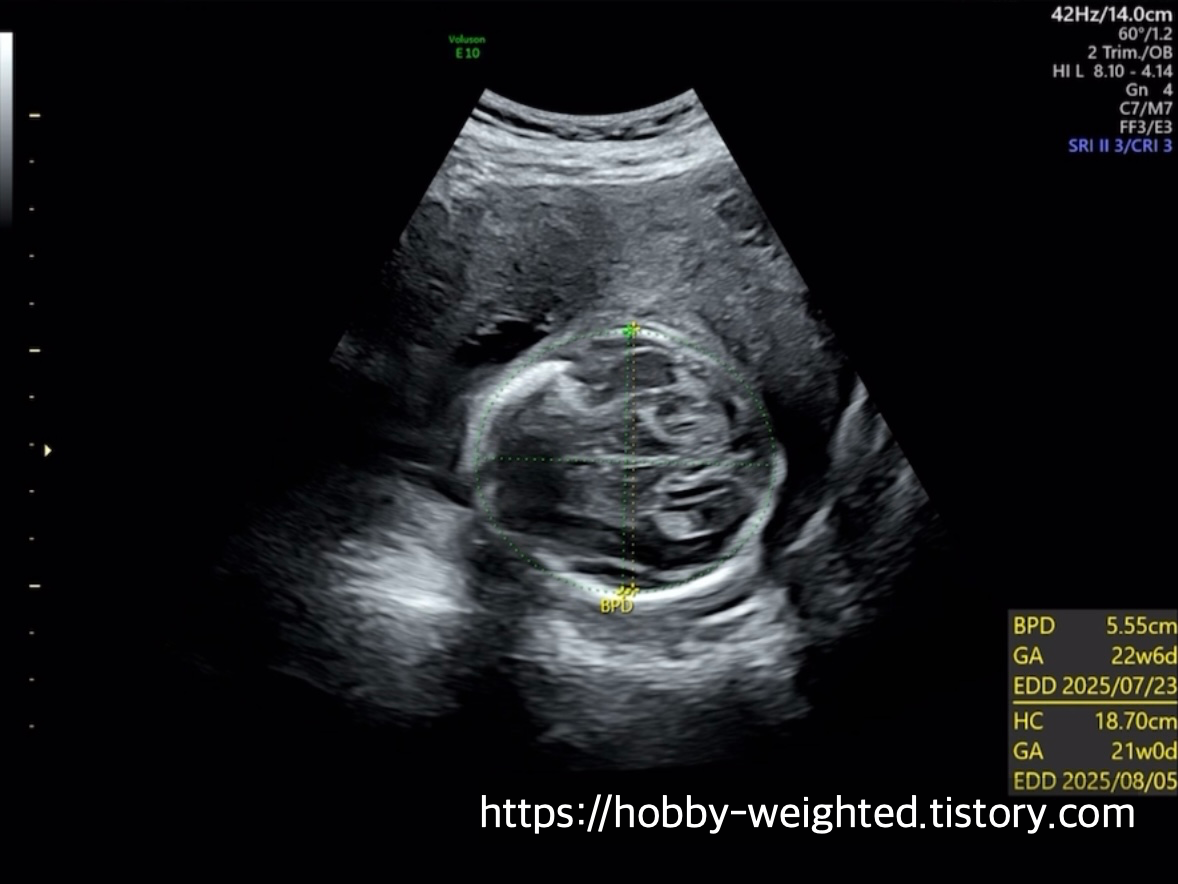

기본 정보(머리둘레, 몸통둘레, 허벅지뼈 길이)

· BPD(Biparietal Diameter): 양쪽 머리뼈 사이 거리(머리 가로 폭)

· HC(Head Circumference): 머리 둘레 전체 측정

전체적인 성장 정도를 판단한다(434g이다 ㅋㅋㅋ 귀여워).